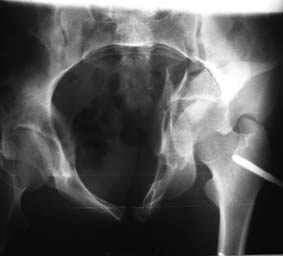

Re: Повреждение вертлужной впадины 2,5 мес.

Это обзорные и косые снимки